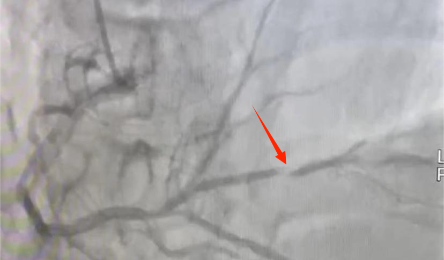

小血管病變,無相(xiàng)應支架可(kě)選,遂決定在病變部位給予藥物球囊治療。手術(shù)成功結束,張某再無心絞痛發作(zuò)。 傳統觀念裡(lǐ),談到冠心病介入治療,很多人(rén)的第一反應就(jiù)是放(fàng)支架,其實,在介入治療中,還(hái)...

近日(rì),通用環球中鐵西安醫院心血管病院一病區主任何麗團隊順利完成首例冠脈血管内超聲(IVUS),标志着我院成功突破冠狀動脈腔内影(yǐng)像學檢查的壁壘,邁進了冠心病精準介入診療新時代。 患者情況 ...